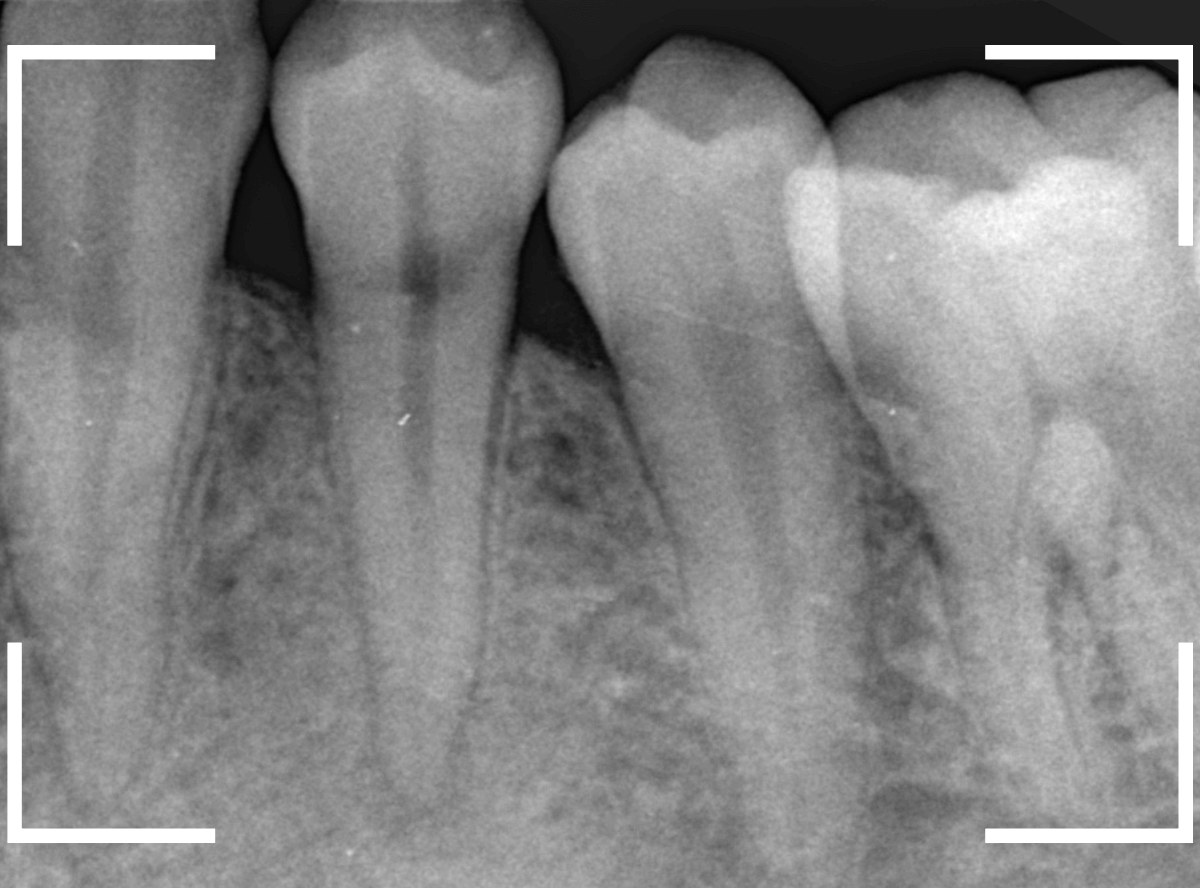

レントゲン写真ももう一度確認してみます。

もしかすると、歯肉の中で虫歯が広がってるのかもしれません。

側面からの虫歯ですので、どれくらい虫歯が深いのかはこの写真からはわかりません。